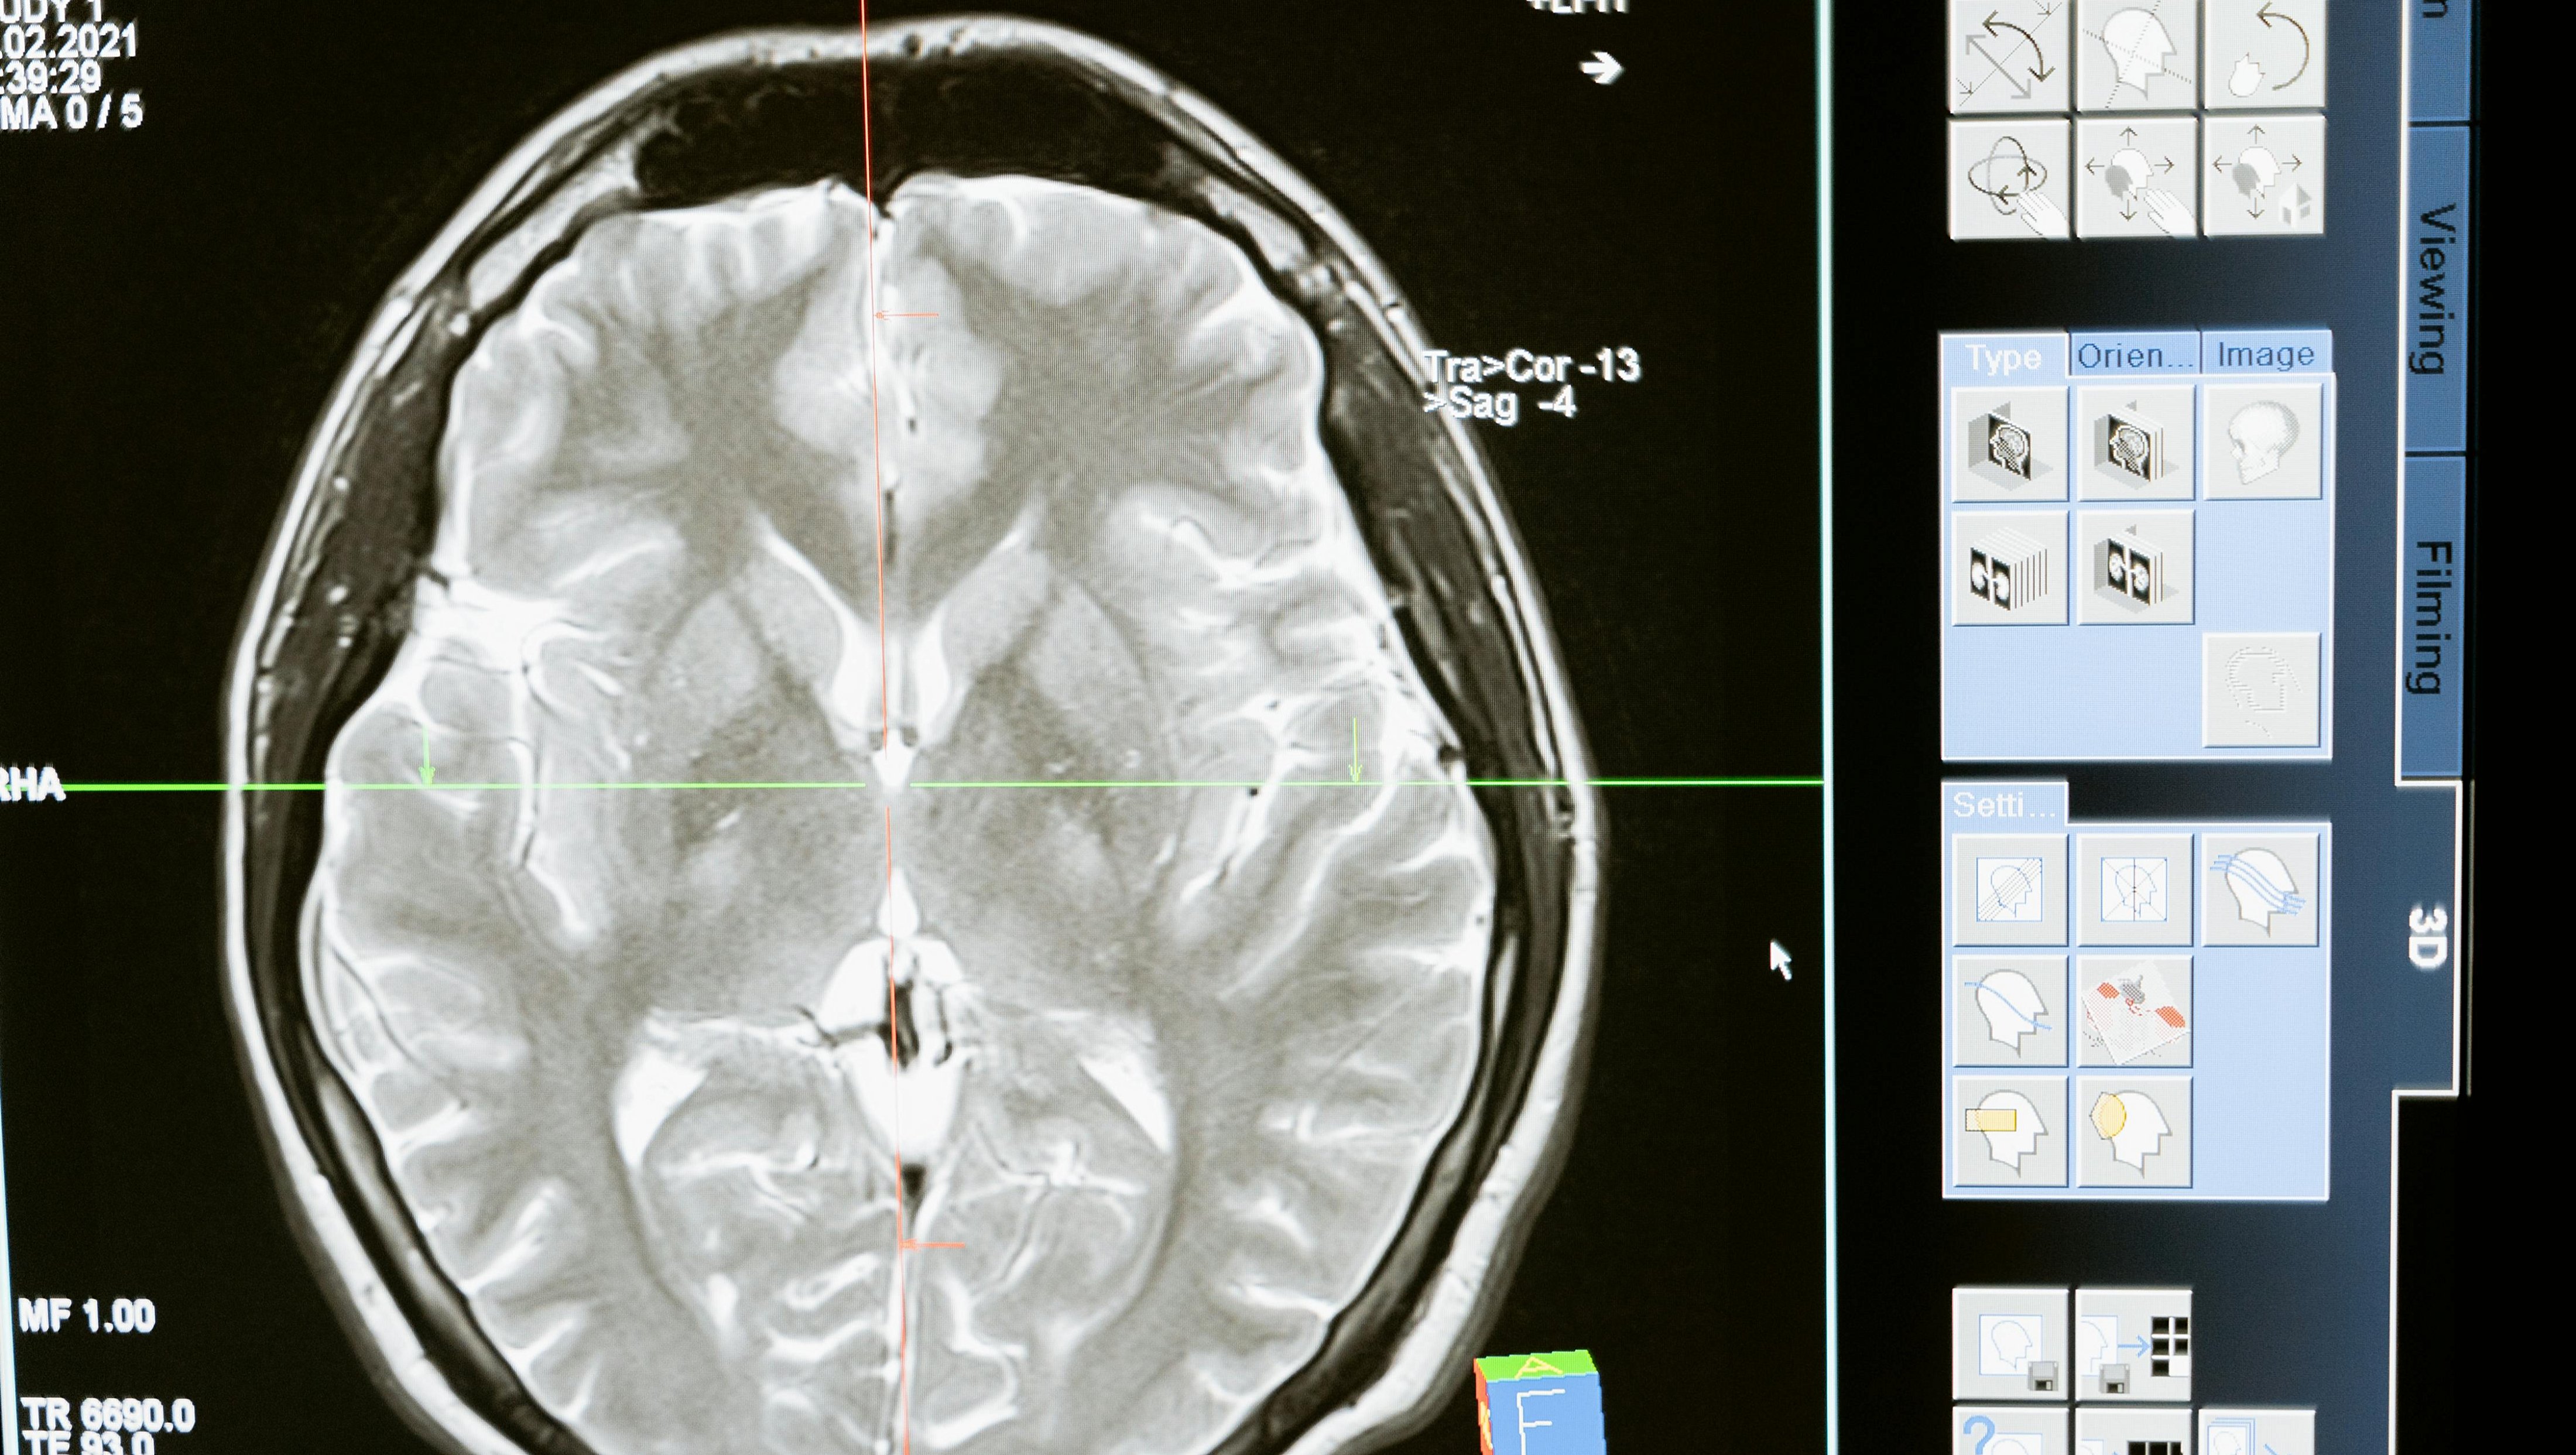

Nörolojik hastalıkların tanısı, genellikle bir dizi test ve inceleme gerektirir. Beyin görüntüleme teknikleri, MR (manyetik rezonans), BT (bilgisayarlı tomografi) gibi araçlarla yapılır. Ayrıca EEG (elektroensefalogram) gibi testlerle beyin dalgaları incelenir.